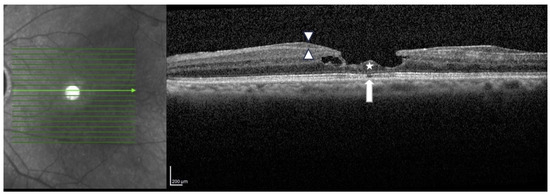

1. Introduction

2. Material and Methods